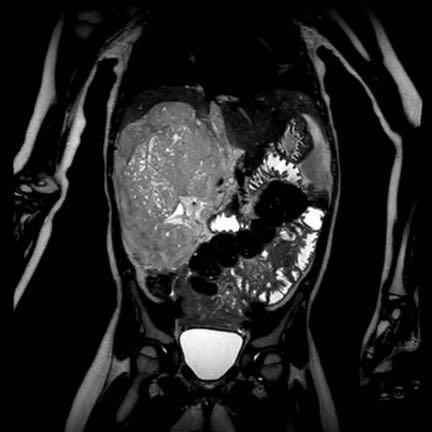

Ca lâm sàng 1

Hình ảnh chuỗi xung T2W mặt phẳng coronal cho thấy một khối u không đồng nhất ở thận trái với các thành phần nang nhỏ.

Khối u ngấm thuốc kém hơn so với phần nhu mô thận bình thường còn lại ở ngoại vi.

Các thành phần đặc của khối u cho thấy hạn chế khuếch tán rõ rệt (mũi tên).

Đây là u Wilms ở bé trai năm tuổi. Hóa trị tiền phẫu được thực hiện theo phác đồ Umbrella của SIOP-RTSG, sau đó tiến hành cắt thận.